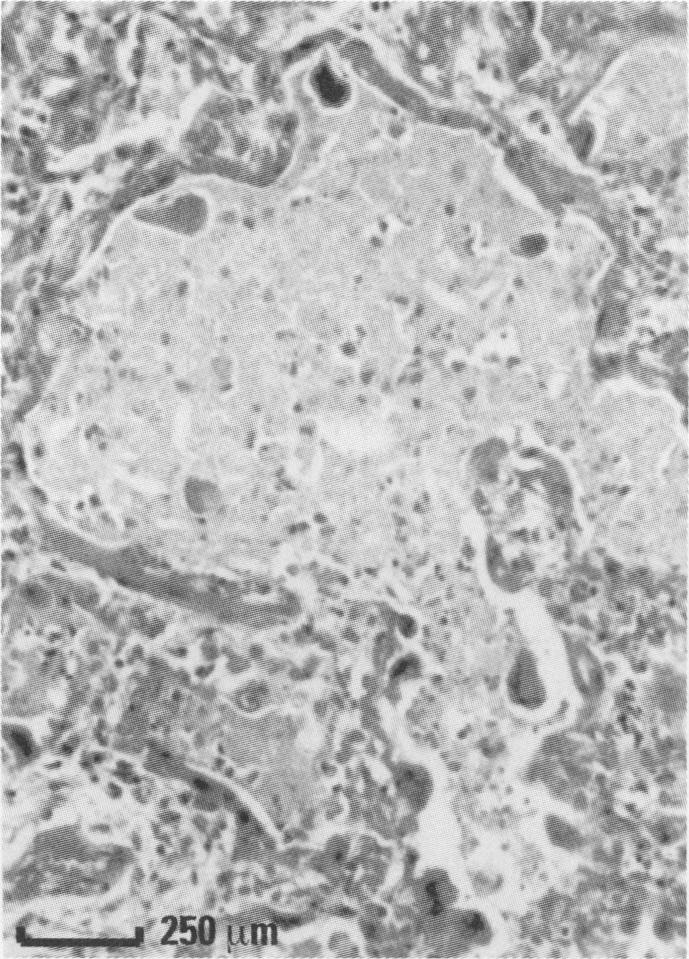

Description:Exposure to coal mine dust and/or crystalline silica results in pneumoconiosis with initiation and progression of pulmonary fibrosis. This review presents characteristics of simple and complicated coal workers' pneumoconiosis (CWP) as well as pathologic indices of acute and chronic silicosis by summarizing results of in vitro, animal, and human investigations. These results support four basic mechanisms in the etiology of CWP and silicosis: a) direct cytotoxicity of coal dust or silica, resulting in lung cell damage, release of lipases and proteases, and eventual lung scarring; b) activation of oxidant production by pulmonary phagocytes, which overwhelms the antioxidant defenses and leads to lipid peroxidation, protein nitrosation, cell injury, and lung scarring; c) activation of mediator release from alveolar macrophages and epithelial cells, which leads to recruitment of polymorphonuclear leukocytes and macrophages, resulting in the production of proinflammatory cytokines and reactive species and in further lung injury and scarring; d) secretion of growth factors from alveolar macrophages and epithelial cells, stimulating fibroblast proliferation and eventual scarring. Results of in vitro and animal studies provide a basis for proposing these mechanisms for the initiation and progression of pneumoconiosis. Data obtained from exposed workers lend support to these mechanisms. [Description provided by NIOSH]